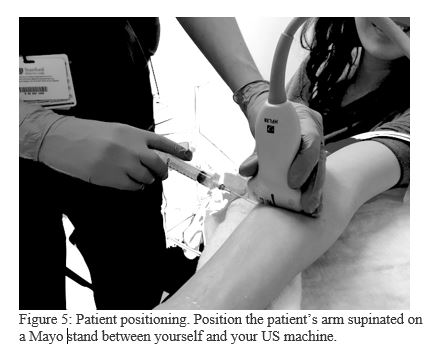

5. Position yourself and your patient (Figure 5)

Spend sufficient time setting up for the procedure. If you and your patient are comfortable, you are more likely to perform a safe and successful block. Rest the patient’s arm on a mayo stand for greater stability. Position the ultrasound machine in front of you, don’t look sideways or backwards over your shoulder. The patient’s arm will be between you and your US machine.